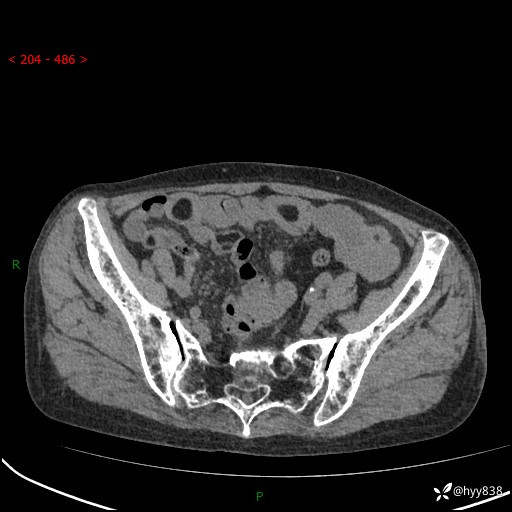

全腹部CT平扫